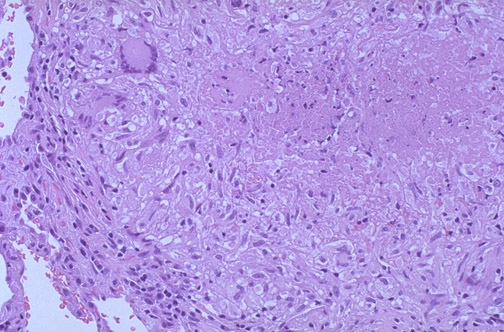

| The edge of a pulmonary granuloma is shown here at medium power magnification. Amorphous pink caseous material composed of the necrotic elements of the granuloma as well as the infectious organisms is present. This area is ringed by the inflammatory component with epithelioid cells, lymphocytes, and fibroblasts. A Langhans giant cell is seen as well. |